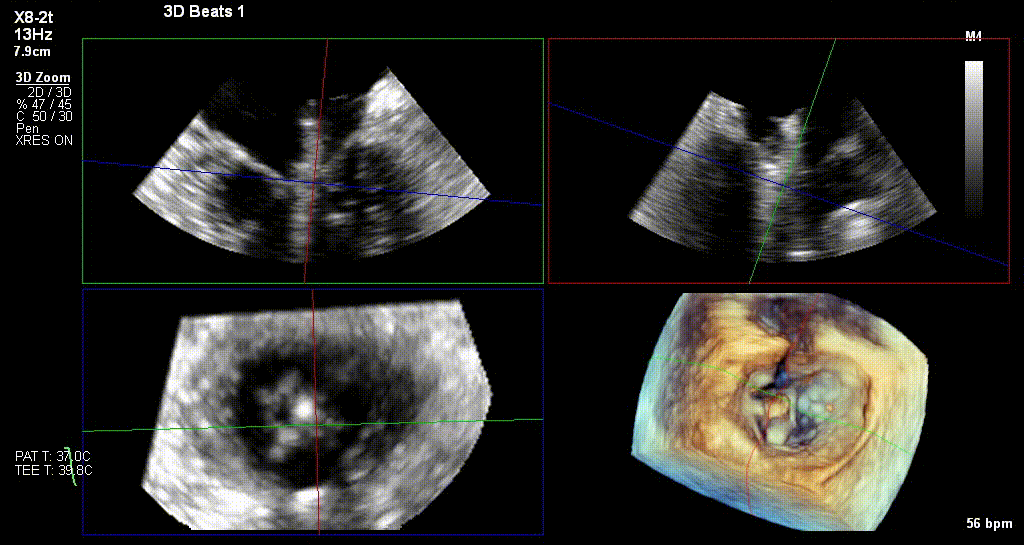

反复测试二尖瓣夹的稳定性,食道超声复查提示二尖瓣夹C1区反流有效改善,术后反流量由术前的4+变为术后的<1,遂精准释放二尖瓣夹。